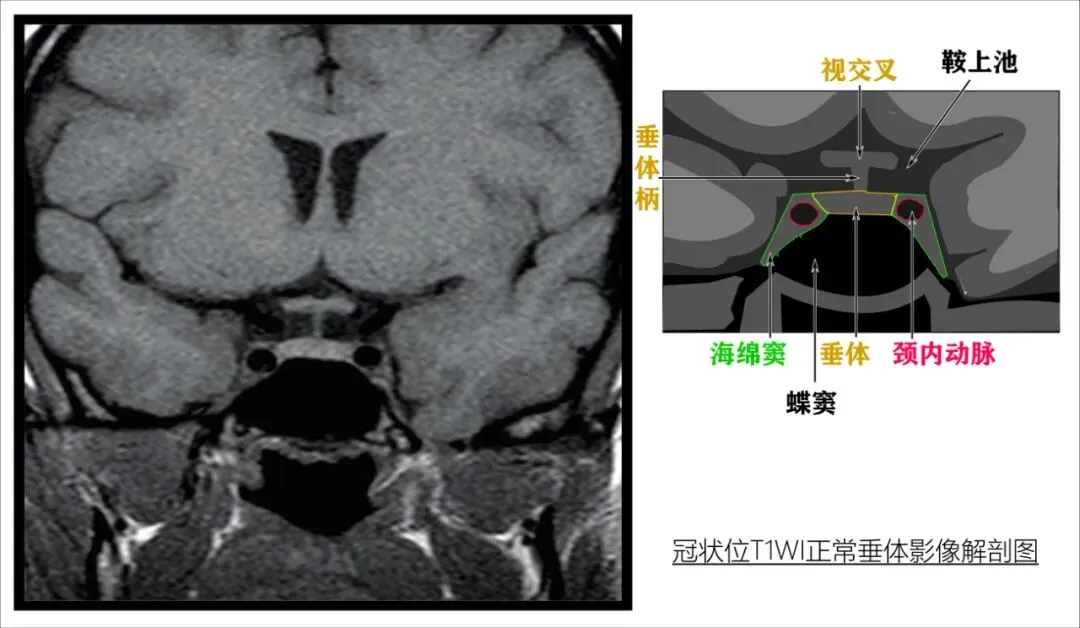

T1WI适合观察解剖结构,观察视交叉、垂体柄、垂体、海绵窦、蝶窦等关系非常好。

注意,在SE-T1WI上神经垂体表现为高信号,不要误以为是病变。

2. 冠状位